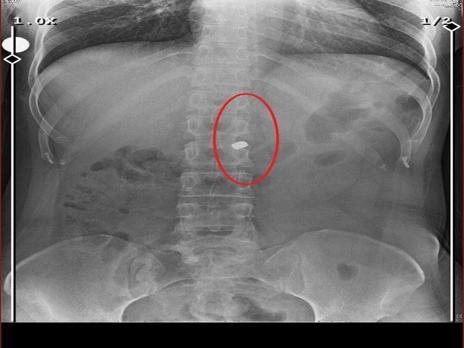

İlyas Sarıkaya, sevgilisi Fatma O.'yu da 8 kurşunla vurup, yaraladı. Arkadaşı Özaslan'ın cesedini önce çarşafa sonra da streç filme sarıp bantlayan Sarıkaya, eczaneden aldığı sargı bezi ve ilaçlarla pansumanını yaptığı sevgilisine yaralı haldeyken 21 gün boyunca cinsel saldırıda bulundu.

Fatma O., annesine yazdığı mesajda, "Odada ceset var. Telefon dinleniyor. Bana 8 el ateş etti. Yaralıyım. Polisi görürse önce beni öldürecek. Onu parayla kandırıp, evden çıkartın. Sonra da beni alın' dedi. Fatma O.’nun annesi, bu mesaj sonrası polise gidip şikayette bulundu. Polis, Fatma O.'nun annesi aracılığıyla Sarıkaya ile iletişime geçti. Fatma O.'nun annesi, telefonla aradığı Sarıkaya'yı, kızına para götürmesi için evine çağırdı. Ekipler, parayı almaya gelen Sarıkaya'yı kendilerine silah çekmesine rağmen yakaladi. Eve giden ekipler, ağır yaralı haldeki Fatma O. ve kokmaya başlayan cesetle karşılaştı.